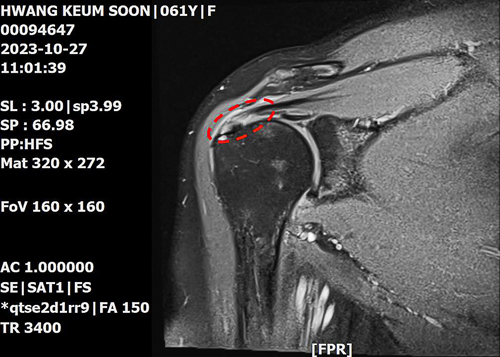

But the pain got worse and I could not move my arm properly. I went to the hospital for MRI and the result showed tendon rupture in my right shoulder and frozen shoulder. I was scheduled to have surgery in late December. But I decided not to have it because I believed God would be able to heal me.

Rotator cuff tear